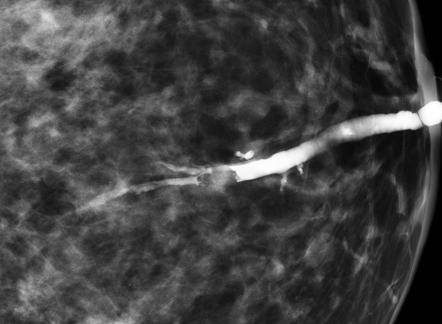

- Mammography reveals no abnormality in most cases but may show duct ectasia, microcalcifications, or a mass.